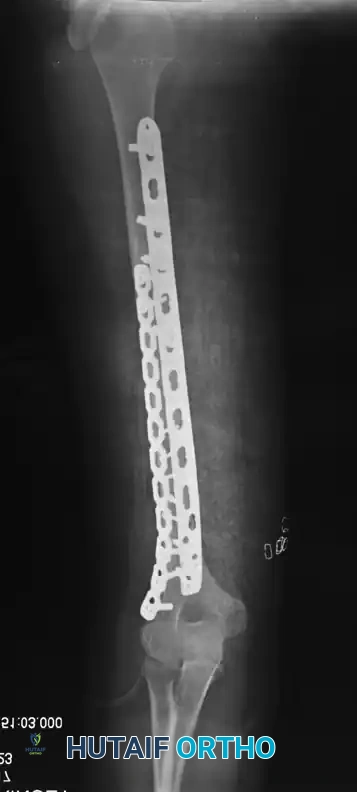

Figure 57-37 A: Displaced humeral shaft fracture.

Figure 57-37 B: After fixation with mini-fragment plate (Eglseder technique) and definitive compression plating.